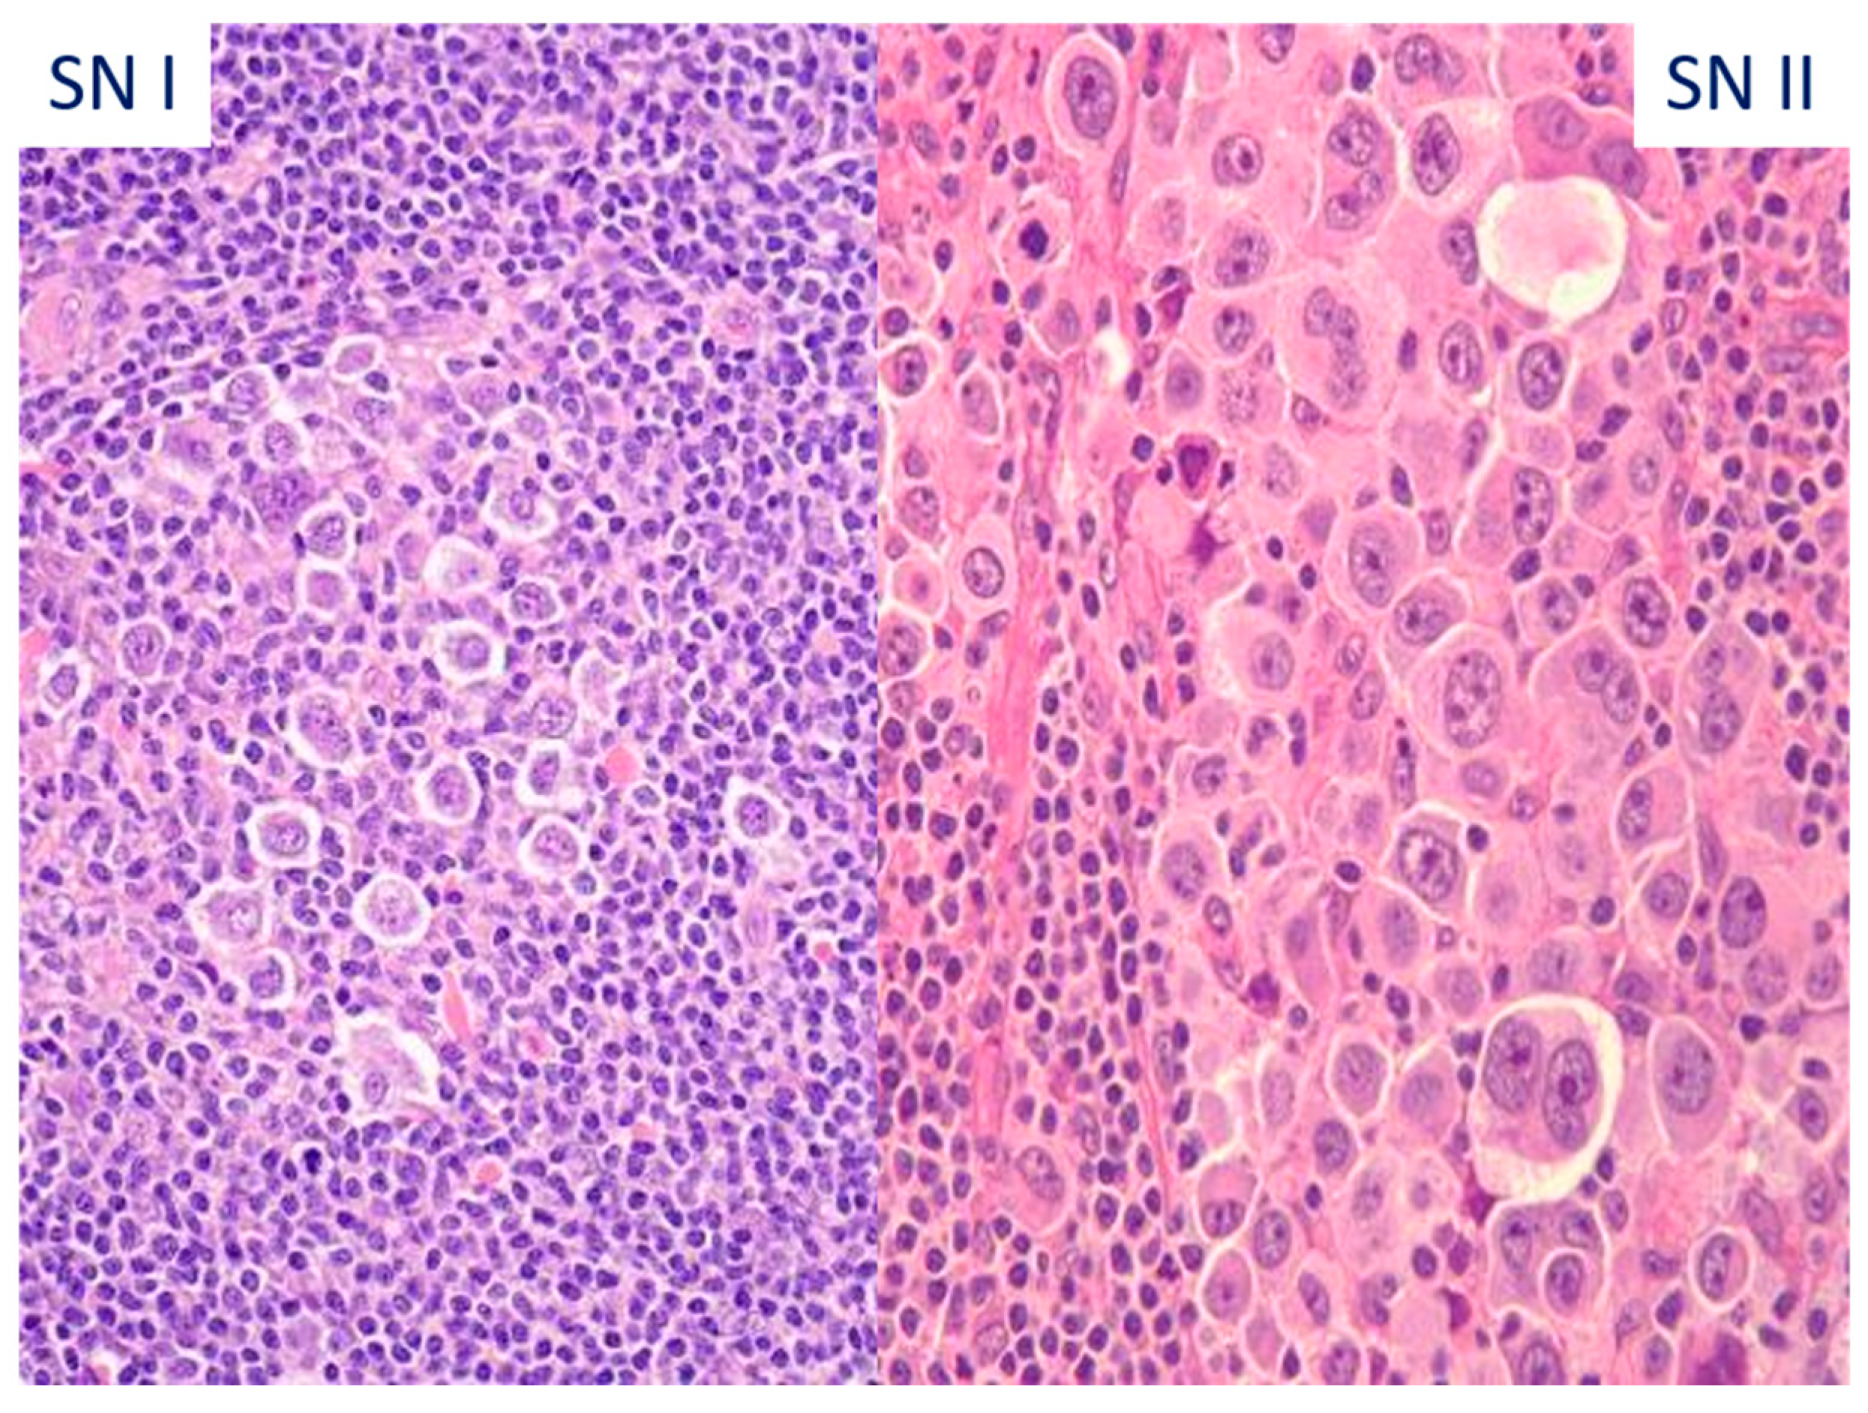

| Differential Diagnosis with Large-Cell Lymphoma: |

| Neoplastic cells | LP cells | RS and mononuclear cells | Centroblasts, immunoblasts, RS, and LP-like cells |

| Tumor microenvironment | B cells > T cells, TFH cells, dendritic cells, histiocytes | T cells in most cases (B cells > T cells in LR variant), eosinophils, histiocytes, neutrophils, and plasmacells | T cells and histiocytes |

| Growth pattern | Nodular, nodular and diffuse | Nodular and/or diffuse; variable sclerosis | Diffuse or vaguely nodular |

| Tumor cell phenotype | Pan B-cell markers (CD20, CD79a, PAX5, OCT2, BOB1)+, CD15 and CD30− (rarely+), LCA+ CD10−, bcl-6+, MUM1−, PU.1+, STAT6−, MEF2B+ EBV− (rare cases+) | Pan B-cell markers (CD20, CD79a, OCT2, BOB1)−, except for PAX5 (faint), CD15 and CD30+ (rarely−, LCA−, CD10−, bcl-6−/+, MUM1+, PU.1−, STAT6+, MEF2B− EBV+ (40%) | Pan B-cell markers (CD19, CD20, CD79a, PAX5, OCT2, BOB1)+, CD15 and CD30−, LCA+ CD10−, bcl-6+, MUM1+/−, PU.1−, EBV− |